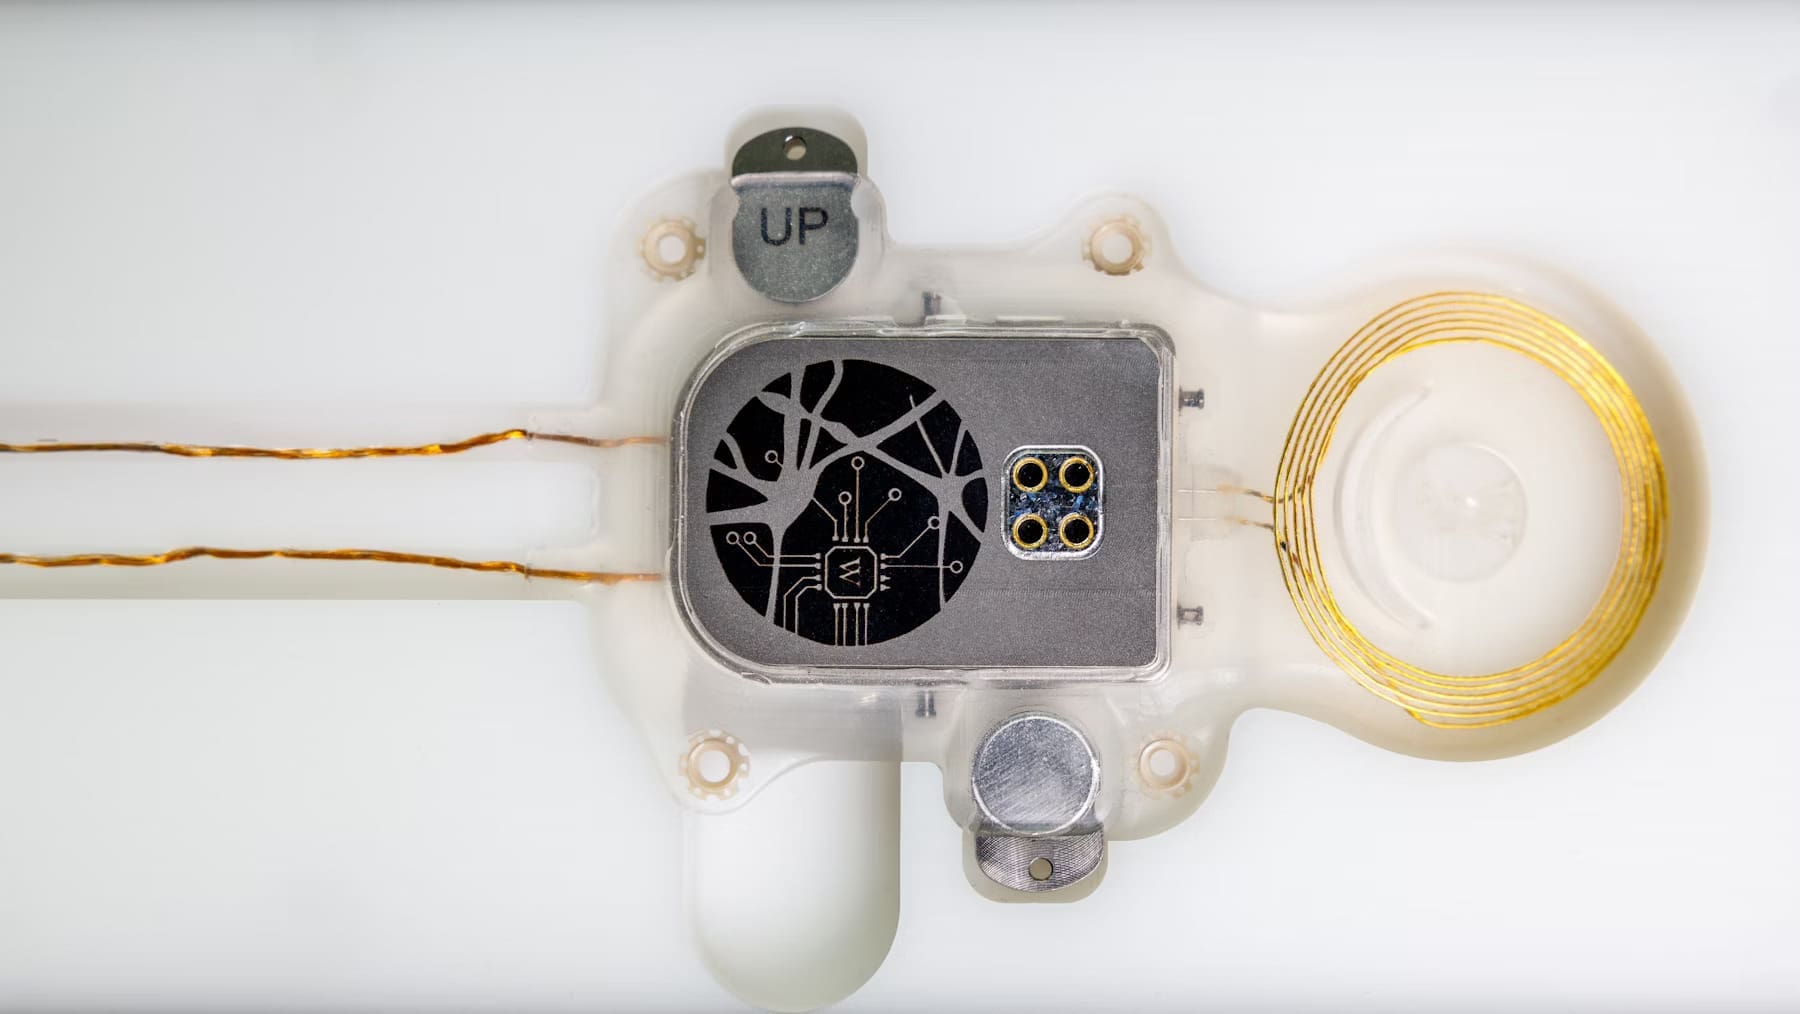

ABILITY enters preclinical trial

A preclinical trial is underway with the ABILITY brain-computer interface system.

The study, which is being carried out in sheep, is a crucial step towards development of a fully implantable device to enable applications such as communication and movement for people with paralysis.

The trial will assess the safety and feasibility of brain signal recording and wireless transfer of neural data to a wearable computer.